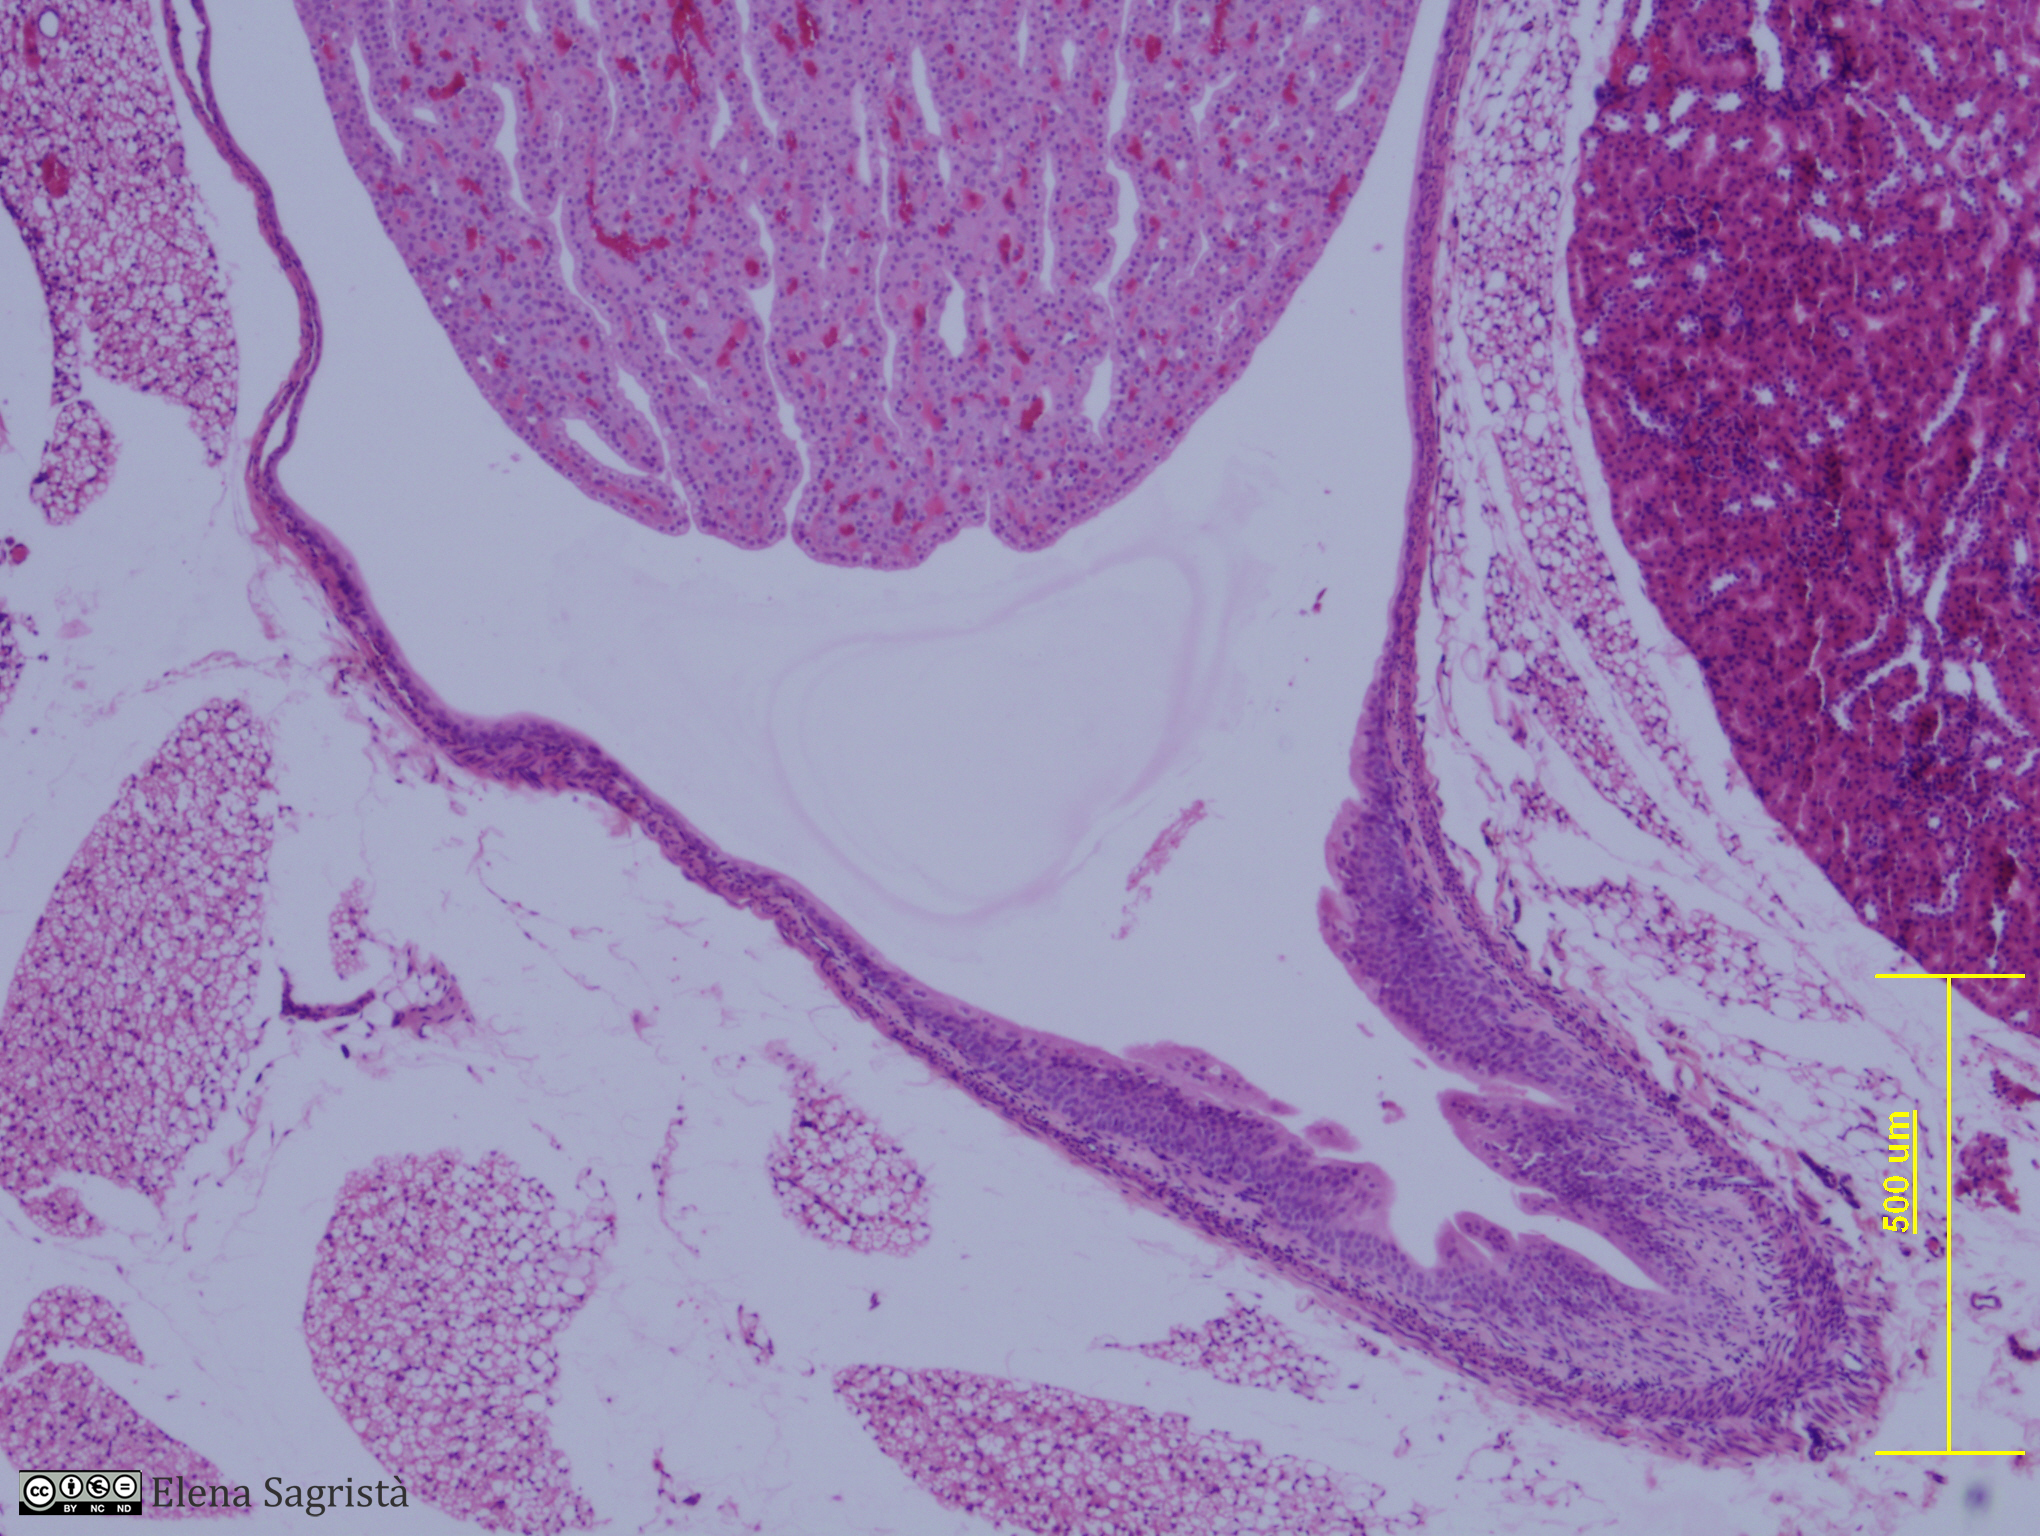

Histologia imatges: 21 Ronyò i Bufeta

Imatges de preparacions histològiques de Ronyò i Bufeta. Microscopia òptica.